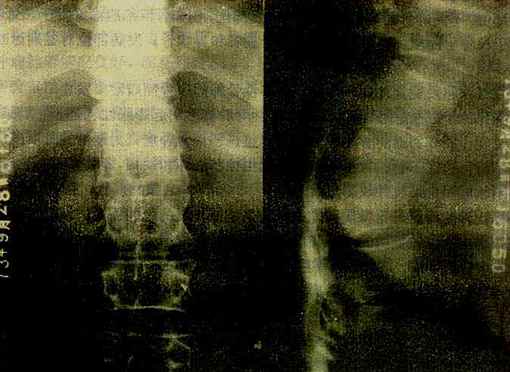

图2-1-22 脊椎结核

胸12与腰1椎体破坏、融合,两椎体间不见椎间隙,于该处有后突变形,

于右侧可见腰大肌脓肿,并有钙化

椎体结核主要引起骨松质的破坏。由于骨质破坏和脊柱承重的关系,椎体塌陷变扁或呈楔形。由于病变开始多累及椎体的上下缘及邻近软骨板,较早就引起软骨板破坏,而侵入椎间盘,使椎间隙变窄,甚至消失和椎体互相嵌入融合而难于分辨(图2-1-22)。病变广泛。常出现后突变形。病变在破坏骨质时可产生大量干酪样物质流入脊柱周围软组织中而形成冷性脓肿。腰椎结核干酪样物质顺一侧或两侧腰大肌引流,称为腰大肌脓肿,表现为腰大肌轮廓不清或呈弧形突出。胸椎结核的脓肿在胸椎两旁,形成椎旁脓肿,表现为局限性梭形软组织肿胀,边缘清楚。在颈椎,则使咽后壁软组织增厚,并呈弧形前突,侧位上易于观察。冷性脓肿较久可有不规则形钙化

总之,脊椎结核的主要X线变化是椎体骨质破坏,变形,椎间隙变窄或消失和冷性脓肿的出现。同椎体压缩性骨折的楔状变形一般不难鉴别,后者无骨质破坏,椎间隙不变窄,更无冷性脓肿表现,而且有清楚的外伤史。